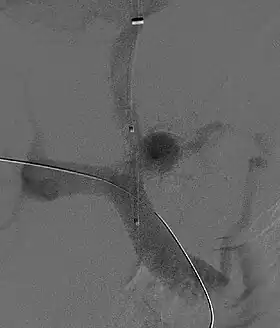

Fluoroscopic image of TIPS in progress. A catheter has been passed into the hepatic vein and after needle puncture, a guidewire was passed into a portal vein branch. The tract was dilated with a balloon, and contrast injected. A self-expandable metallic stent has yet to be placed over the wire.